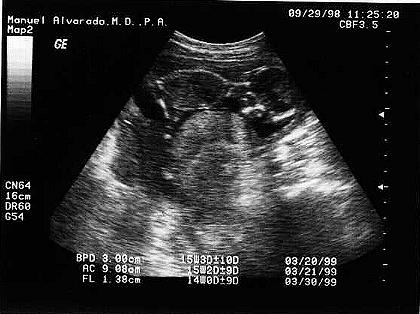

My Ultrasound Pictures!!